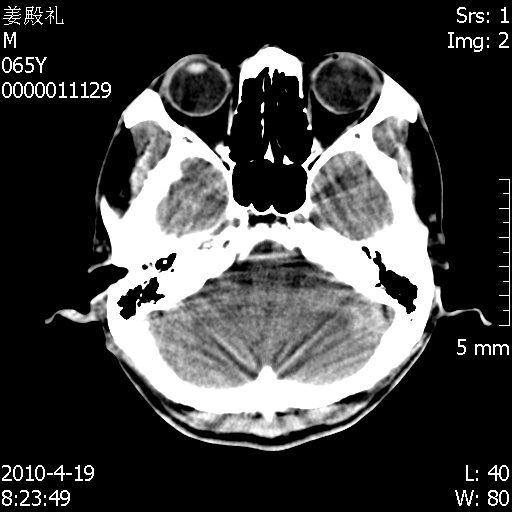

老年男性,突发左下肢无力1天,其余有价值的检查都没有。平扫ct值大约60hu,增强后ct值没什么改变,请大家讨论一下这个病例是什么?说明诊断理由。

左小脑、右大脑顶叶多发圆形高密度病灶,其周环状低密度影。考虑多发脑出血。隔期观察。

至于是出血还是微小钙化所致的高密度无法考证,三个都出血也不是一点都不可能,同一种组织学类型的肿瘤受到同一个外来的因素影响后会表现出相同的病理变化。说实在的,我本身支持转移瘤的,就是想不通为什么不强化?我认为单纯脑出血的边缘不会那么光滑,并且那也不是出血的常见部位,多发也不常见。

刚刚复习了转移瘤的不典型ct征象,有4条,分享给大家:

1、高密度灶:多为瘤内有较多沙粒体钙化所致,而不是出血,ct值可高达95hu;

2、无强化;

3、无水肿;

4、无占位效应。